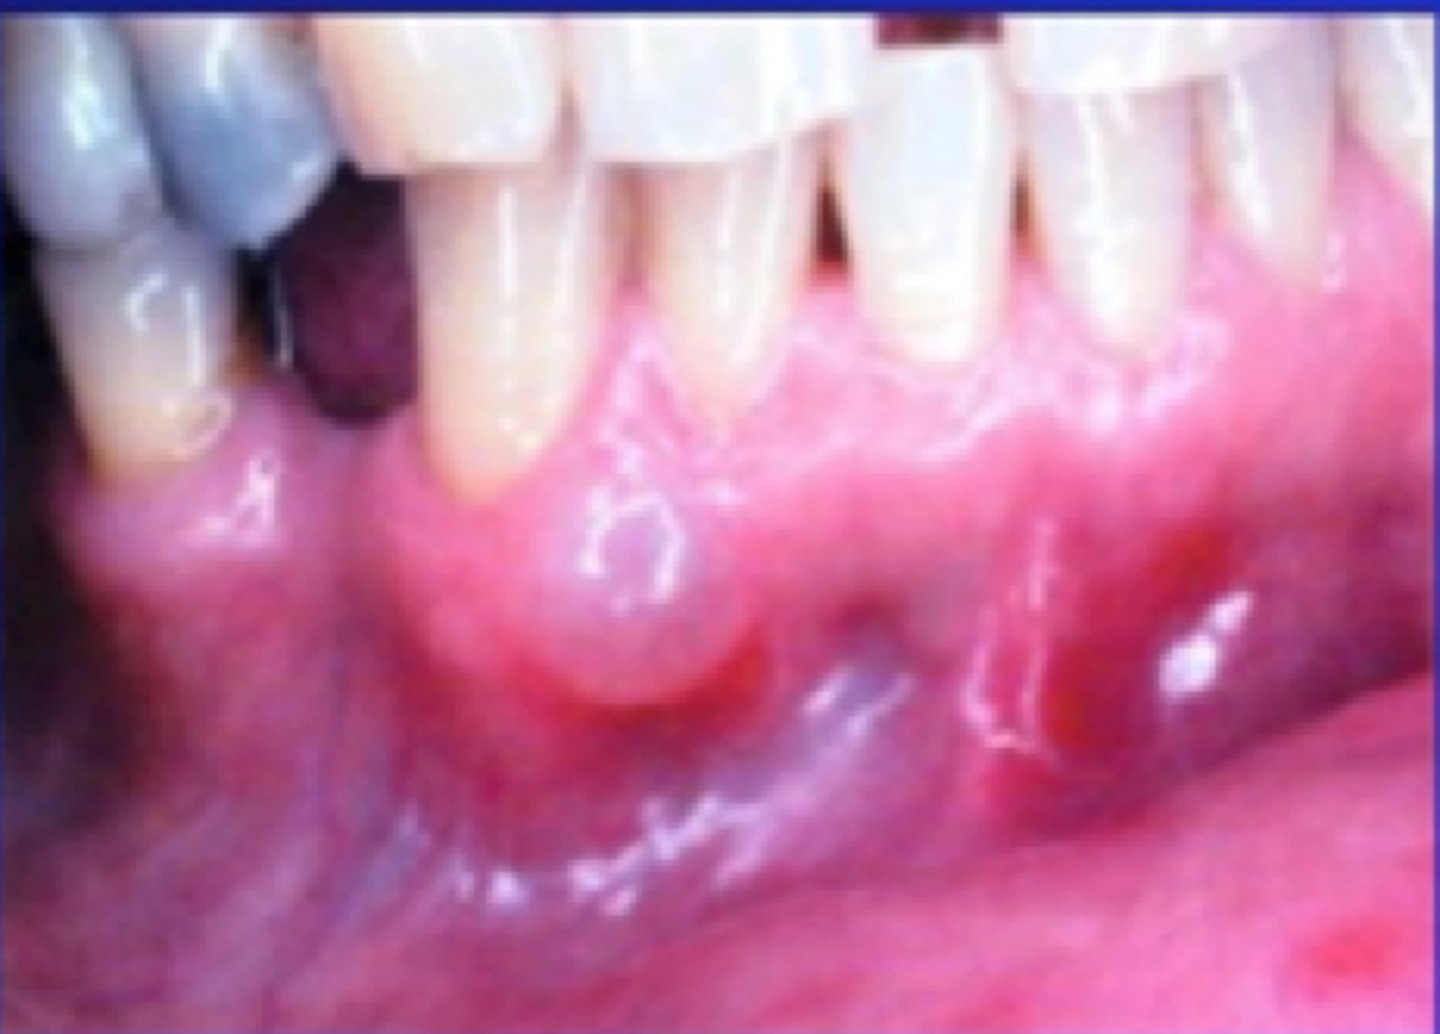

What is erosive lichen planus? (+ common locations, population)

PAINFUL

⢠red area surrounded by white striae

⢠shallow ulcers or desquamative gingivitis

⢠bilateral

⢠skin lesions

⢠common locations: buccal mucosa, gingiva, tongue

⢠population: middle-aged females